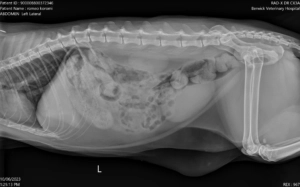

After his hospital stay, Romeo returned to the clinic for a follow-up visit. More radiographs were performed to assess the effectiveness of the treatment and ongoing medications. Though there was still some faecal matter in his colon which was expected, it was not causing the same impaction and discomfort as before, thanks to the intervention and care he had received.